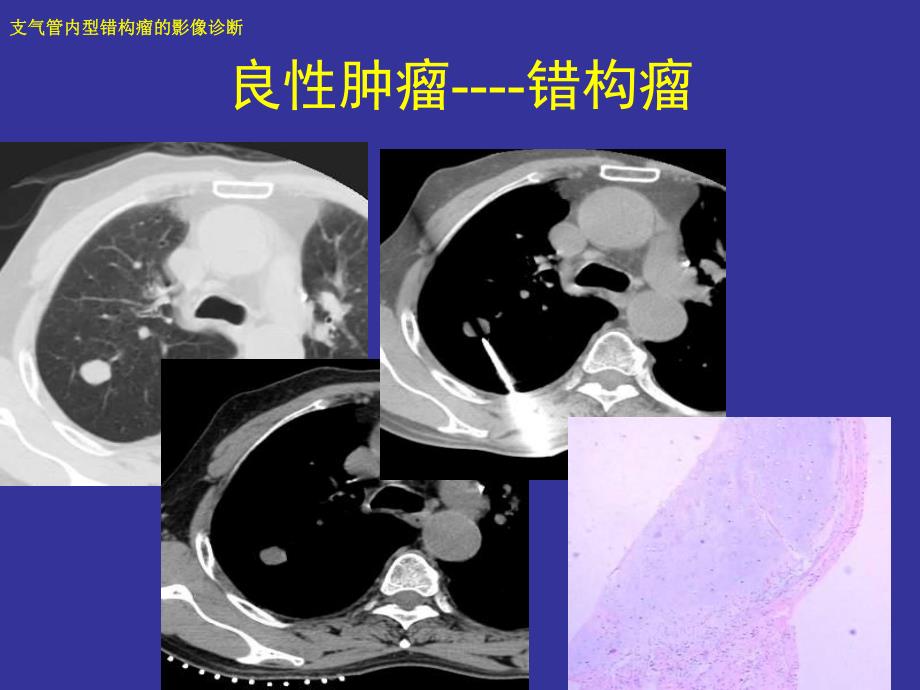

1、1/30支气管内型错构瘤的影像诊断支气管内型错构瘤的影像诊断 良性肿瘤-错构瘤2/30支气管内型错构瘤的影像诊断支气管内型错构瘤的影像诊断 错构瘤3/30支气管内型错构瘤的影像诊断支气管内型错构瘤的影像诊断 误诊中央型肺癌4/30支气管内型错构瘤的影像诊断支气管内型错构瘤的影像诊断 误诊中央型肺癌5/30支气管内型错构瘤的影像诊断支气管内型错构瘤的影像诊断 支气管内型错构瘤误诊率很高 我院共6例,误诊5例 诊断肺癌2例 诊断炎症3例 诊断支气管内良性病变1例6/30支气管内型错构瘤的影像诊断支气管内型错构瘤的影像诊断 支气管内型错构瘤误诊率很高 文献:支气管内型错构瘤4例报告及国内其他42例分

3、诊断 如何诊断?支气管内型与肺内型错构瘤是相同的肿瘤,均源于支气管黏膜下的未分化间叶组织 原始间叶组织化生形成的骨、软骨、脂肪及平滑肌等 支气管内型位于较大的支气管内,引起肺内继发改变 肺内型发生在细小支气管内,表现为肺内良性结节影 肺内型错构瘤也应看作是管内型肿瘤9/30支气管内型错构瘤的影像诊断支气管内型错构瘤的影像诊断 临床特征 本病可发生在主支气管、叶支气管及段支气管。主要由软骨和腺体组织组成,也可含有大量脂肪 可发生于任何年龄,以40-60岁居多 男女比例为24:110/30支气管内型错构瘤的影像诊断支气管内型错构瘤的影像诊断 影像学表现-11、向支气管腔内突出,表面光滑,窄基底与支

4、气管壁相连的软组织结节影,支气管壁未见明显增厚11/30支气管内型错构瘤的影像诊断支气管内型错构瘤的影像诊断 向支气管腔内突出,支气管壁未见明显增厚12/30支气管内型错构瘤的影像诊断支气管内型错构瘤的影像诊断 向支气管腔内突出,支气管壁未见明显增厚13/30支气管内型错构瘤的影像诊断支气管内型错构瘤的影像诊断 向支气管腔内突出,支气管壁未见明显增厚14/30支气管内型错构瘤的影像诊断支气管内型错构瘤的影像诊断 向支气管腔内突出,支气管壁未见明显增厚15/30支气管内型错构瘤的影像诊断支气管内型错构瘤的影像诊断 气管腺癌16/30支气管内型错构瘤的影像诊断支气管内型错构瘤的影像诊断 肺癌-支气